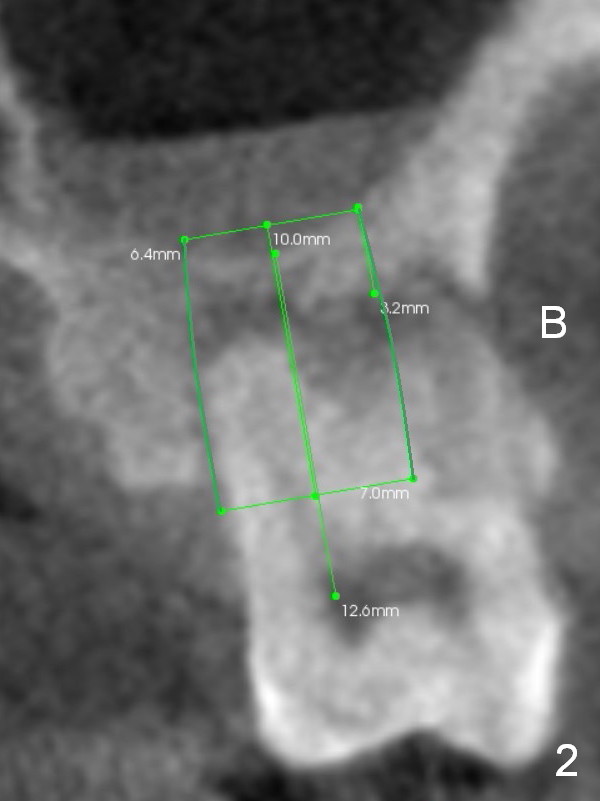

A 42-year-old lady (HJ) has advanced periodontitis at #15 (Fig.1 (CBCT sagittal section)). The buccal (B) plate is thin (Fig. 2 (coronal section), 3 (axial section)). The apical bone is also thin (Fig.1,2). A 7x10 mm implant is placed in a position so that the implant contacts the mesial, palatal and distal walls of the socket (treated with 2% Xylocaine with 1:50,000 Epinephrine) for primary stability (Fig.3). The buccal gap will be filled with Osteogen Plug apically (Fig.4 purple rectangles) and bone graft coronally (red circles). SM implant (Fig.4) is more tapered than UF one (Fig.2), easier to insert.